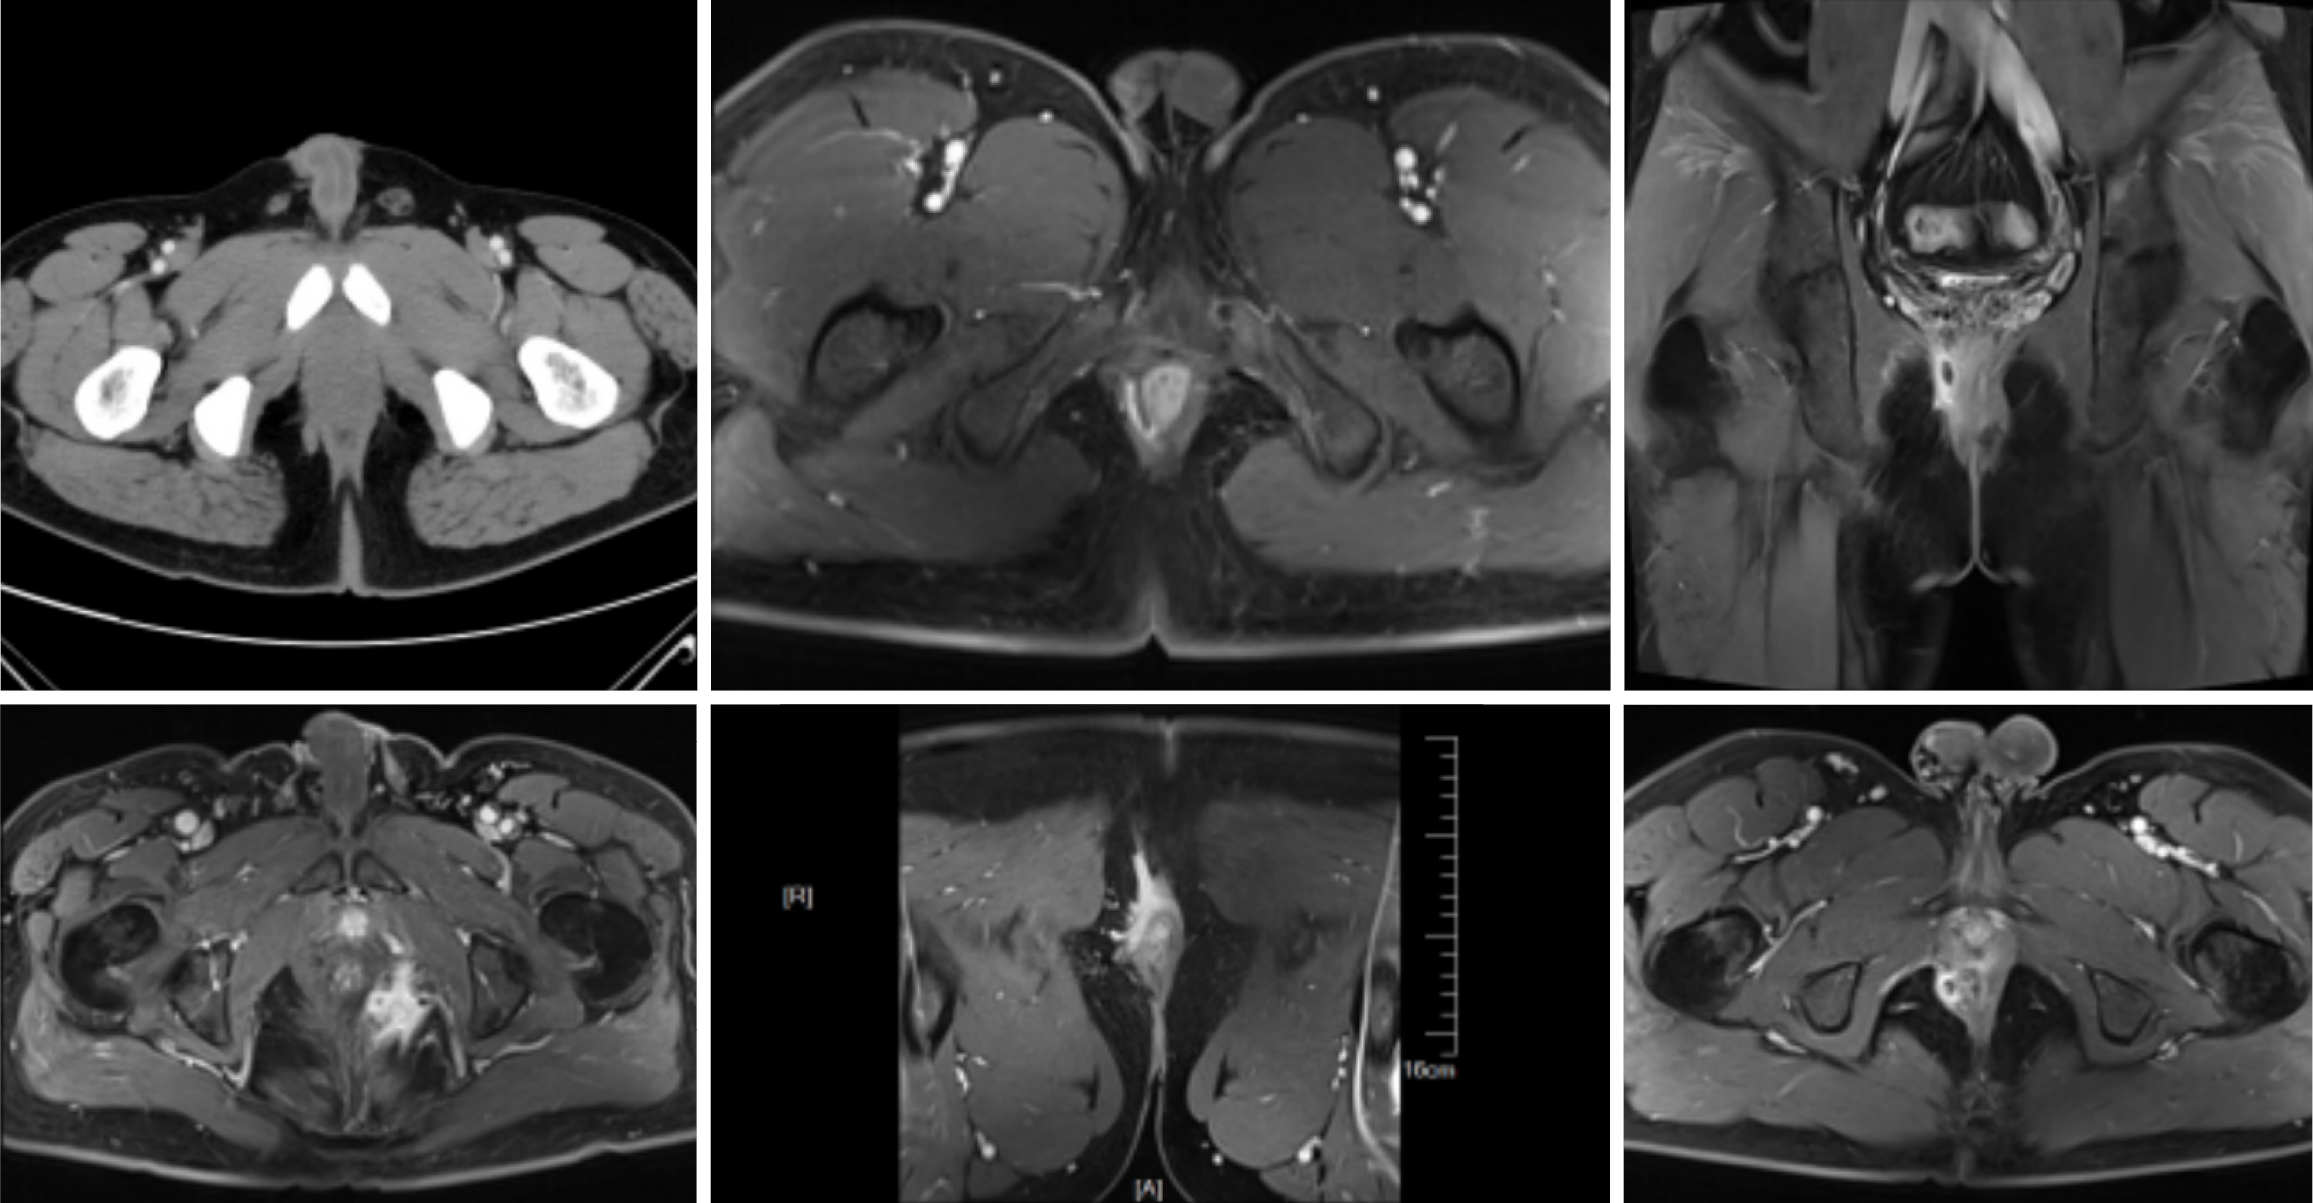

A total of 119 patients were included in this study. Based on the different diagnostic methods used, the patients were divided into three groups: The MSCT group (undergoing MSCT, n = 25), the 1.5T MRI group (undergoing 1.5T MRI, n = 45), and the 3.0T MRI group (undergoing 3.0T MRI, n = 49). Sex, age, disease duration, and body mass index (BMI) showed no statistically significant differences among the three groups (P > 0.05 L; Figure 1 and Table 2).